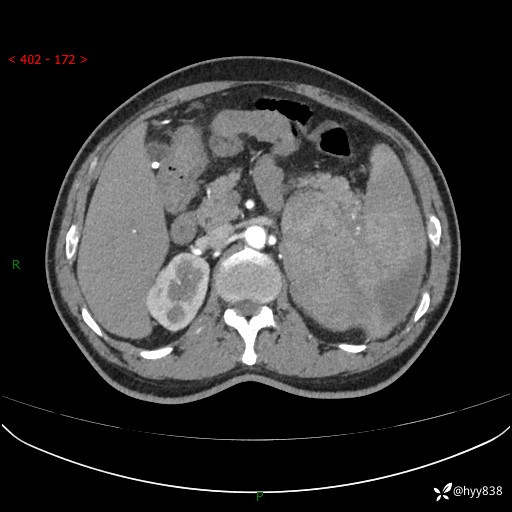

上腹部CT平扫

增强(动脉期+静脉期)